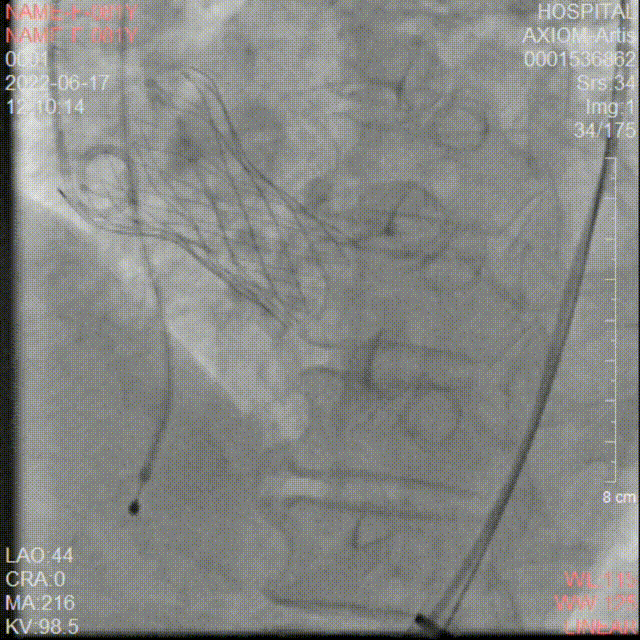

冠脉造影检查